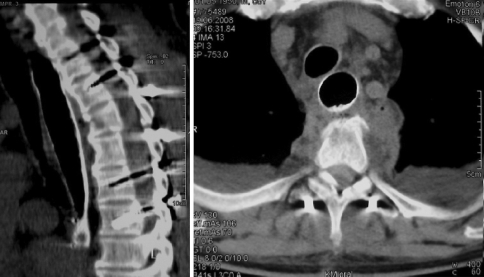

Fig. 2.

Computed tomography of the chest obtained after septic decompensation of the patient with abscess formation and peri-oesophageal air inclusions at the level of the fractured vertebrae